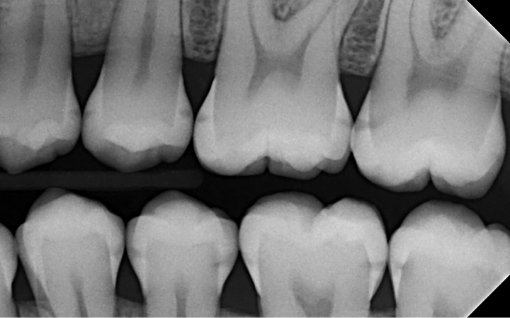

2. What surface require restoration?